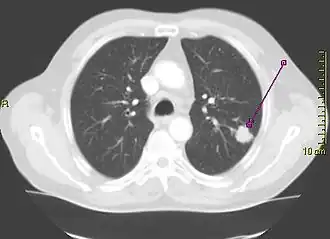

Longkanker wordt meestal veroorzaakt door roken. Hierbij worden de longen langdurig blootgesteld aan tabaksrook,[3] dat de oorzaak is van 80-90% van alle gevallen van longkanker.[2] Niet-rokers vormen 10-15% van de longkankerpatiënten[4] en deze gevallen worden vaak toegeschreven aan meeroken,[5][6] genetische factoren,[7] radongas,[7] asbest[8] en luchtvervuiling of een combinatie daarvan.[7] Longkanker is te zien op een röntgenfoto van de borstkas en met computertomografie (CT-scan). De diagnose wordt bevestigd met een biopsie[9] die doorgaans wordt uitgevoerd via bronchoscopie of onder CT-geleiding. De behandeling en het langetermijnresultaat hangen af van het type kanker, het stadium (mate van verspreiding) en de algehele gezondheid van de patiënt.

Een van de eerste onderzoeken bij iemand met symptomen die op longkanker kunnen wijzen, is een röntgenfoto van de borstkas. Daarop kan een duidelijke massa (tumor), verwijding van het mediastinum (wat kan wijzen op uitzaaiingen in de lymfeklieren), atelectase (samenvallen van de long), consolidatie of pleuravocht te zien zijn.[3] Meestal wordt met een CT-scan meer informatie over het type en de ernst van de ziekte verzameld. Vaak wordt met een bronchoscopie of CT-geleide biopsie een stukje weefsel van de tumor genomen voor histologisch- of pathologisch onderzoek.[16]

Longkanker ziet er op een röntgenfoto van de borstkas vaak uit als een zwelling. De differentiële diagnose is echter breed. Veel andere ziekten geven hetzelfde beeld, waaronder tuberculose, schimmelinfecties, uitzaaiingen van kanker elders in het lichaam of een longontsteking (pneumonie). Zeldzame oorzaken van een zwelling zijn onder meer hamartomen, bronchogene cysten, adenomen, arterioveneuze misvorming, pulmonaire sekwestratie, reuma knobbel, ziekte van Wegener of een goedaardige zwelling van de lymfeklier (lymfoom).[34] Longkanker kan ook toevallig worden ontdekt als een zwelling (een incidentaloom) wanneer om een geheel andere reden een röntgenfoto of een CT-scan van de borstkas is gemaakt.[35] De definitieve diagnose van longkanker is gebaseerd op het histologische onderzoek van het verdachte weefsel samen met de symptomen en radiologische kenmerken.[2]